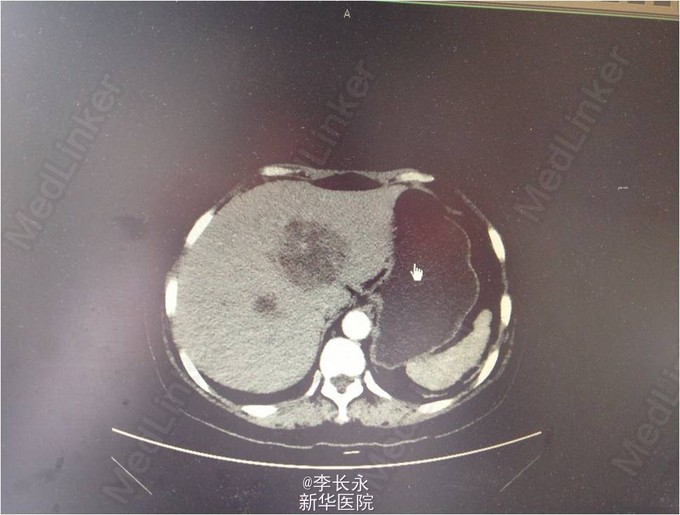

女,54岁。 患者入院前3天无明显诱因下突然出现发热,体温最高达40度,并伴有恶心呕吐,呕吐物为胃内容物,无咳嗽、腹痛腹泻等,急诊予患者抗感染、退热等治疗,患者体温恢复正常,遂回家休养,但夜间患者体温再次上升到39度。为求进一步诊治 查体:神清,气平,双瞳孔等大等圆,对光(+),HR 85次/分,律齐,未及杂音。两肺呼吸音粗,未及明显干湿罗音。腹软无压痛,肝脾肋下未及,肠鸣音正常。 辅检:CRP 106 mg/L |白细胞计数 19.00 10^9/L|中性粒细胞% 83.6 %|红细胞计数 4.52 10^12/L|血红蛋白 138 g/L|血小板计数 182.00 10^9/L 上腹部CT增强:肝内多发低密度灶,肝脓肿首先考虑,双肾小结石 诊断:肝脓肿 双肾小结石 治疗经过:予患者抗感染、保肝、调节免疫及吸氧等对症支持治疗。入院后患者诊断肝脓肿可能,故考虑行超声下穿刺,但超声科表示:“肝脓肿伴液化不全,不宜行穿刺引流置管术”,经积极抗感染治疗后,患者脓腔逐步缩小,患者体温逐步下降,无明显腹痛、腹胀,故予以出院。 随访:出院后各项生命体征平稳。 总结:肝脓肿分为三种类型,其中细菌性肝脓肿常为多种细菌所致的混合感染,约为80%,未穿刺不能明确诊断,对症处理,定期随访